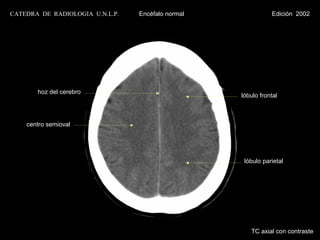

CATEDRA DE RADIOLOGIA U.N.L.P.   Encéfalo normal            Edición 2002

cisura interhemisférica

cuerpo calloso

ventrículo lateral                              septum pelucidum

centro semioval

plexo coroideo                                  glándula pineal

calcificado                                     calcificada

asta occipital

seno longitudinal inferior

seno longitudinal superior

TC axial con contraste